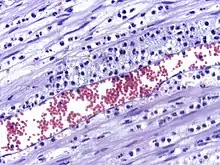

Leukocyte extravasation (also commonly known as leukocyte adhesion cascade or diapedesis – the passage of cells through the intact vessel wall) is the movement of leukocytes out of the circulatory system and towards the site of tissue damage or infection. This process forms part of the innate immune response, involving the recruitment of non-specific leukocytes. Monocytes also use this process in the absence of infection or tissue damage during their development into macrophages.

The cytoskeletons of the leukocytes are reorganized in such a way that the leukocytes are spread out over the endothelial cells. In this form, leukocytes extend pseudopodia and pass through gaps between endothelial cells. This passage of cells through the intact vessel wall is called diapedesis.[3] These gaps can form through interactions of the leukocytes with the endothelium, but also autonomously through endothelial mechanics.[4] Transmigration of the leukocyte occurs as PECAM proteins, found on the leukocyte and endothelial cell surfaces, interact and effectively pull the cell through the endothelium. Once through the endothelium, the leukocyte must penetrate the basement membrane. The mechanism for penetration is disputed, but may involve proteolytic digestion of the membrane, mechanical force, or both.[5] The entire process of blood vessel escape is known as diapedesis. Once in the interstitial fluid, leukocytes migrate along a chemotactic gradient towards the site of injury or infection.